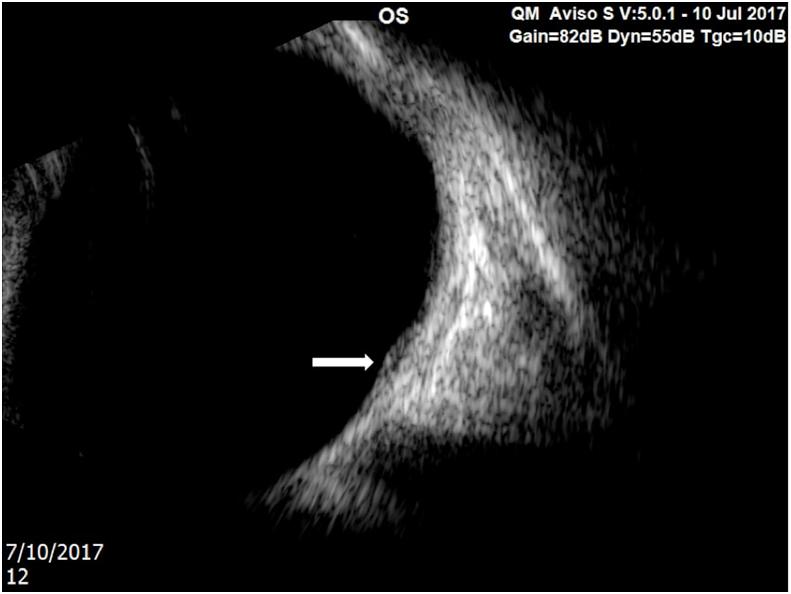

A one year-old boy with a history of Terson syndrome due to a motor vehicle accident presented three months after trauma with a white feather-shaped membrane in the left macula. Preoperative OCT showed a preretinal hyperreflective tissue at the foveal center. The patient underwent pars plana vitrectomy. After separation of the posterior hyaloid, intraoperative OCT did not show any change in structural components. After peeling the ILM, the fibrotic membrane persisted. A bent 30-gauged needle was used to create a plane of dissection in the adherent sub-ILM membrane, which was then peeled with ILM forceps without complication. Post-operative OCT confirmed complete excision without evidence of macular edema. Pathology results indicated presence of fibrocellular tissue that contained hemosiderin, consistent with old organized hemorrhage as a component of the membrane.

Sub-ILM hemorrhage may persist as a tautly adherent fibrotic membrane that can mimic the appearance of an epiretinal membrane or a chronic subhyaloidal hemorrhage during examination, especially in young children. Intraoperative OCT may aid in select complex macular surgery cases to better delineate the planes of dissection during sub-ILM fibrosis excision.